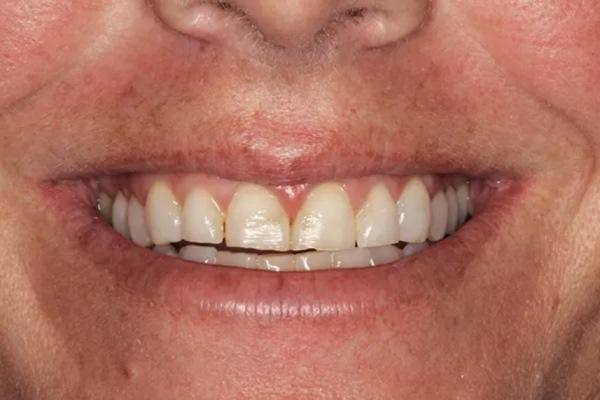

Для постоянной фиксации виниров использовался полупрозрачный цемент (RelyX Veneer Cement, 3M Oral Care) виниры были зафиксированы парами начиная с области центральных резцов, затем латеральные резцы и заканчивая клыками. Каждую реставрацию закрепляли с помощью 3-секундного светового отверждения, а излишки цемента удаляли с помощью ультразвукового скеллера. Окончательное отверждение осуществлялось путем полимерезации светом в течение дополнительных 20 секунд на каждый зуб. Результаты проведённого лечения показаны на фото с 9 по 12. Изменение улыбки пациентки с фиксированными постоянными реставрациями (фото 9). Демонстрация смыкания после лечения (фото 10). Портретная фотография анфас с широкой улыбкой (фото 11). Прицельные снимки зубов пациентки после проведенного лечения (фото 12).

Фото 12